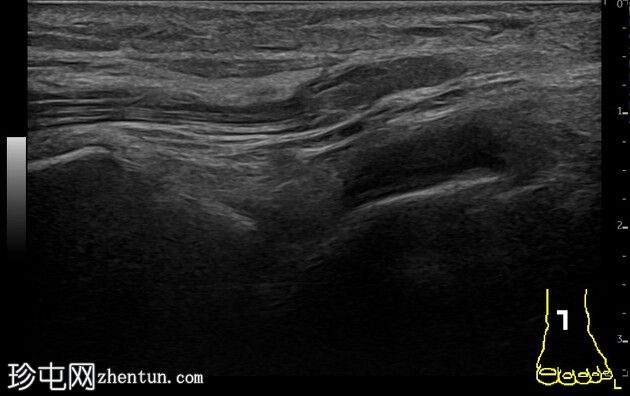

踝关节前隐窝少量积液。患侧腓骨前下胫腓韧带撕脱。与对侧(右侧)相比,患侧韧带水肿。左侧腓骨远端骨骺增宽,邻近干骺端区域骨膜下少量出血。对侧(右侧)腓骨远端骨骺正常。距腓前韧带和跟腓韧带完整。跟骨前突未见撕脱。

本病例展示了超声在儿童踝关节损伤诊断中的应用价值。与健侧进行对比有助于诊断。